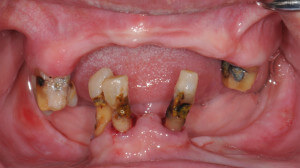

婆婆剛來的時候口腔狀況很差,長期配戴的活動假牙早已經鬆動不合,口內僅存的幾顆牙齒也岌岌可危

婆婆很節省,一直說年紀大了,不用花大錢做牙齒,唯一的希望就是可以吃個銅鑼燒.幫她檢查了剩餘的牙齒,因為牙周病與蛀牙的緣故,口內的牙齒必須全部拔除.在有限的預算裡,我們只能用製作全口假牙去恢復咬合功能.